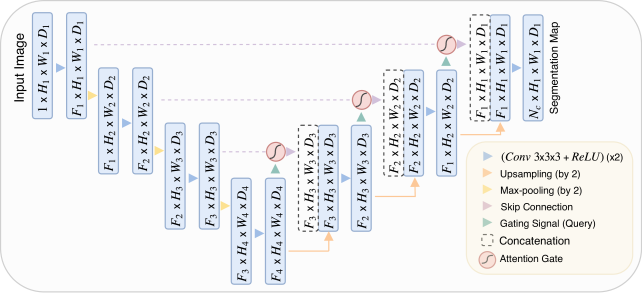

Attention U-Net

Paper: 《Attention U-Net: Learning Where to Look for the Pancreas》

Accepted by MIDL 2018.

文章解读:https://zhuanlan.zhihu.com/p/114471013

Attention U-Net 提出了一种应用于医学影像的基于门控注意力 attention gate 的模型,该模型可以抑制背景区域,强调前景区域,自动学习如何区分目标的外形和尺寸。